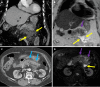

Endoscopic retrograde cholangiopancreatography (ERCP) is a cornerstone procedure for the diagnosis and management of pancreatic and hepatobiliary diseases. Although its diagnostic role has been increasingly supplanted by noninvasive imaging modalities such as magnetic resonance imaging (MRI) and magnetic resonance cholangiopancreatography, the therapeutic applications of ERCP have continued to expand. ERCP is widely used and has a generally favorable safety profile. However, it is important to recognize expected post-procedural imaging findings and serious complications that can arise. The increasing complexity of therapeutic interventions and the growing volume of procedures have led to a higher incidence of complications that often present with overlapping clinical and laboratory features, underscoring the critical role of imaging in differential diagnosis. This review focused on the typical normal ERCP findings and the imaging characteristics of common complications, including pancreatitis, bleeding, ERCP-related infections, perforations, and stent-related complications. Computed tomography (CT) is particularly valuable in timely recognition, management, and surgical decision-making for these complications. Furthermore, MRI offers a radiation-free alternative for managing complications in selected patients. Therefore, radiological modalities, particularly CT and MRI, are critical tools for the rapid diagnosis, management, and surgical decision-making processes for post-ERCP complications.